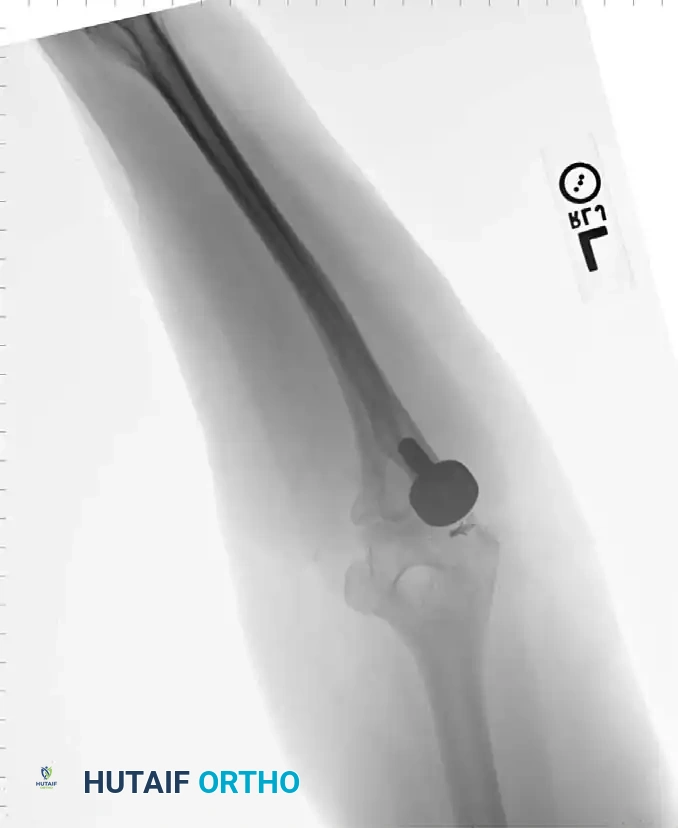

Associated Surgical & Radiographic Imaging